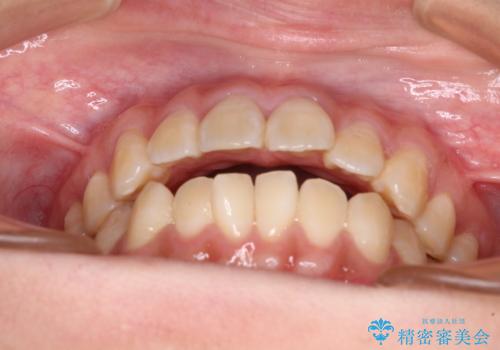

舌の突出癖による開咬と前歯の突出 インビザライン矯正治療

- 上下前歯の非接触と叢生を気にして来院された患者様です。

開咬の改善はインビザラインの最も得意とするところであるため、インビザラインを用いて矯正治療を行うこととしました。

治療開始直後に上顎前歯に激しい痛みが発現し、矯正治療を休んだり、マウスピースの装着時間を短くしたりと工夫をしましたが、残念ながら治療途中で失活していることが分かりました。

矯正治療の途中で前歯の根管治療とオールセラミッククラウンによる補綴治療を行い、その後インビザライン1セットを用いて細かい部分を仕上げました。